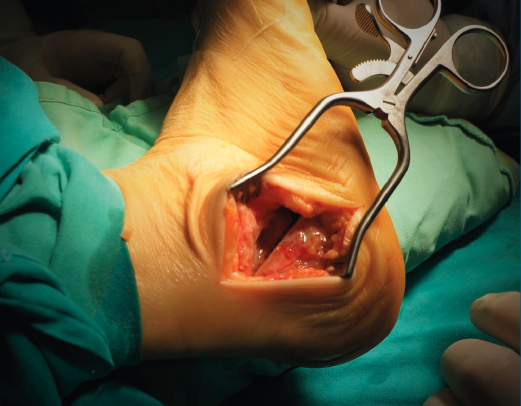

La osteotomía del calcáneo se realiza con el paciente en decúbito lateral con el pie a intervenir expuesto sobre el otro. Cuando queremos valguizar el retropié, el trazo de la osteotomía de tipo Dwyer lo hacemos lo más alejado posible de la inserción del tendón de Aquiles, para así aprovechar una mayor longitud de brazo de palanca para la función del tríceps. Realizamos una cuña de base lateral de aproximadamente 10 mm. En todos los casos buscamos un efecto muy valguizante que conseguimos asociando el efecto Dwyer con una lateralización de la osteotomía (tuberosidad posterior del calcáneo) de unos 8-10 mm (Figura 1). Es importante liberar y estirar bien las partes blandas mediales en el plano de la osteotomía para poder lateralizar la tuberosidad posterior. No es necesario cortar la fascia plantar medial, que es un gesto potencialmente iatrogénico, sino que es suficiente con emplear un minuto estirando la fascia utilizando un separador de láminas con apertura y cierre sucesivos. Una vez conseguido el cierre de la osteotomía y el desplazamiento lateral, utilizamos una pinza grande abierta que clavamos en el seno del tarso y en la tuberosidad posterior del calcáneo para mantener la posición mientras fijamos la osteotomía con 2 tornillos canulados de 6,5 mm (Figura 2). A esta osteotomía que combina un efecto Dwyer con un efecto Koutsogiannis inverso la llamamos coloquialmente osteotomía “supervalguizante” del calcáneo. El apoyo se permite hacia las 3 semanas de la cirugía con una bota ortopédica y bastones.

Figura 2. La utilización de una pinza grande clavada en el seno del tarso y en la tuberosidad posterior del calcáneo permite el mantenimiento de la valguización y facilita la síntesis.